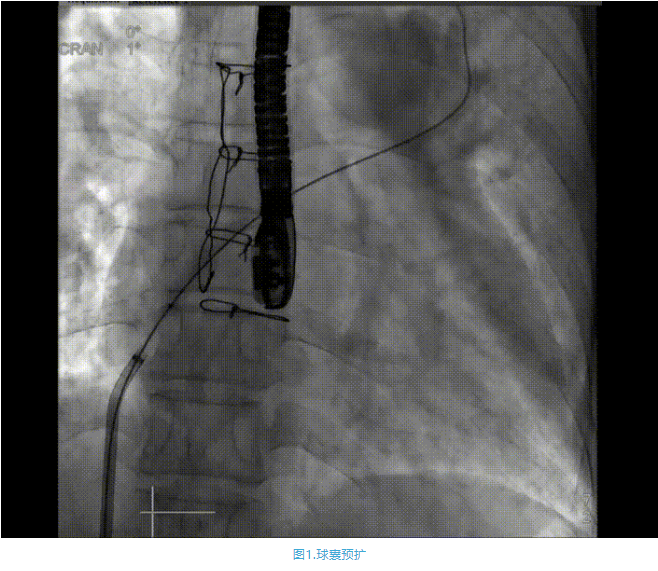

術(shù)中首先在局麻下穿刺股動(dòng)脈、股靜脈,完成心導(dǎo)管檢查評(píng)估后轉(zhuǎn)為全麻,在食道超聲引導(dǎo)下穿刺房間隔,穿刺成功后將加硬導(dǎo)絲送入左上肺靜脈建立軌道,根據(jù)患者病情行球囊預(yù)擴(kuò)張后植入6mm孔徑房間隔造孔支架,經(jīng)透視及食道超聲評(píng)估支架左右盤展開良好,夾持于房間隔兩側(cè),固定穩(wěn)定、位置良好,食道彩超顯示房水平右向左為主分流,分流孔直徑符合預(yù)期大小,心導(dǎo)管檢查評(píng)估達(dá)到預(yù)期效果,釋放造孔支架。術(shù)后12h患者下床活動(dòng),恢復(fù)順利,擬于近日完善術(shù)后評(píng)估后出院。